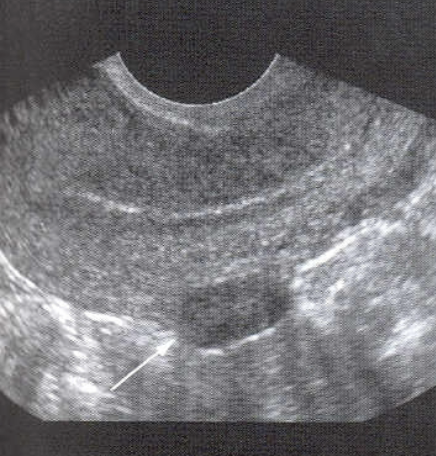

Nabothian Cysts

Considered normal in adults

may be multiple or single

Size ranges from 3mm - 3cm

require no treatment

often occur after pregnancy or chronic cervicitis